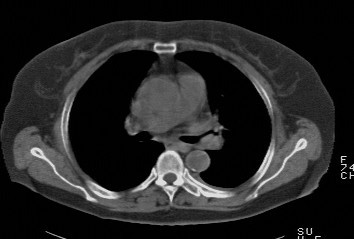

f,74发热咳嗽三天

考虑左肺上叶中央型肺癌并左肺上叶舌段肺不张。

考虑左肺上叶中央型肺癌并左肺上叶舌段肺不张.

左肺上叶舌段肺不张,建议作进一步检查除外中心型肺癌。

左肺上叶舌段肺不张,建议行纤支检查除外中心型肺癌。支持!